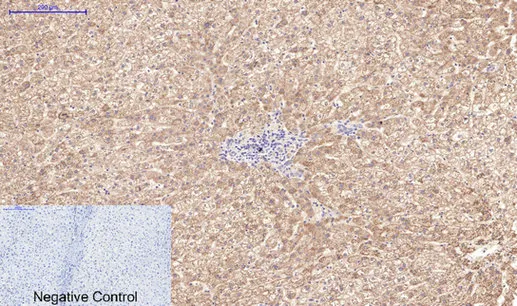

AFP alpha 1 Fetoprotein(17C5)Mouse Monoclonal Antibody

Cat: AMM06666

Size1:50μL Price1:$118

Size2:100μL Price2:$220

Size3:200μL Price3:$380

Application:WB,IHC-P,IF-P,IF-F,ICC/IF

Reactivity:Human

Conjugate:Unconjugated

Optional conjugates: Biotin, FITC (free of charge). See other 26 conjugates.

Gene Name:AFP